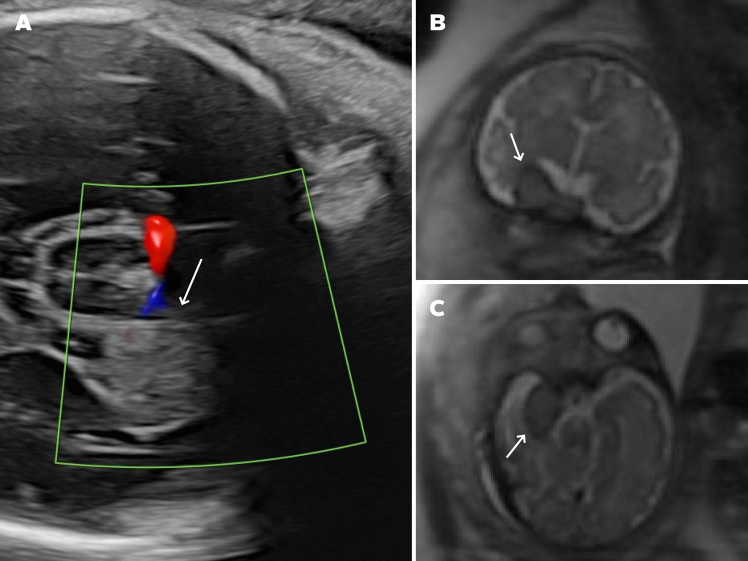

Observations: A 28-year-old female underwent routine fetal ultrasound at 32 weeks' gestation, revealing a 1.8-cm perithalamic lesion. Fetal MRI at 33 weeks confirmed an extra-axial mass in the right middle fossa with a dural attachment. Postnatal MRI on day 1 of life demonstrated imaging features consistent with an IH. Given the neonate's asymptomatic status, conservative management was pursued. Serial MRI at 10 weeks and 6 months showed progressive lesion regression, with near-complete resolution. The infant remained asymptomatic with normal neurodevelopmental progress.